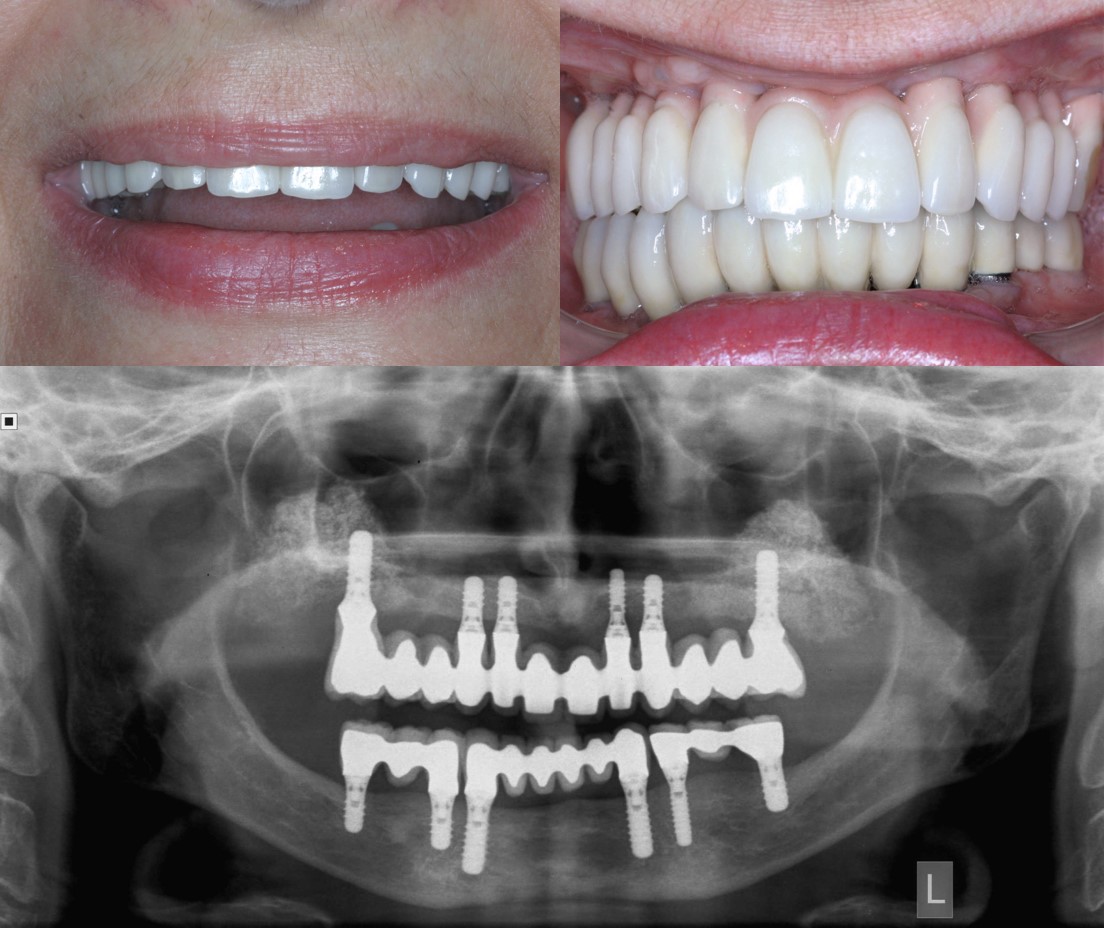

Εκατομμύρια άνθρωποι σε όλο τον κόσμο υποφέρουν από απώλεια δοντιών. Μετά από επιτυχή κλινική εφαρμογή για περισσότερο από 35 έτη, τα οδοντικά εμφυτεύματα αποτελούν σήμερα ένα εξαιρετικό υποκατάστατο των φυσικών δοντιών, με άριστη μακροχρόνια πρόγνωση. Τα εμφυτεύματα είναι κατασκευασμένα από τιτάνιο ή από κράματα τιτανίου με ζιρκονία, τα οποία είναι πλήρως βιοσυμβατά και έχουν καθιερωθεί ως υλικά εκλογής και στον χώρο της Ορθοπαιδικής Χειρουργικής. Μικρά μεταλλικά στηρίγματα - κολοβώματα (abutments) συνδέονται πάνω στα εμφυτεύματα και αποτελούν την πλατφόρμα πάνω στην οποία θα στηριχθούν τα τεχνητά δόντια (Εικόνα 5Α, 5Β). Δουλεύοντας σε συνεργασία με οδοντίατρο—προσθετολόγο (ο οποίος σχεδιάζει και τοποθετεί τα τεχνητά δόντια), ο στοματικός και γναθοπροσωπικός χειρουργός αξιολογεί τον ασθενή και τοποθετεί τα εμφυτεύματα στο οστό των γνάθων (Εικόνα 6).

Σε περιστατικά ολικής αποκατάστασης με οδοντικά εμφυτεύματα, σημαντική βοήθεια προσφέρουν πλέον οι ηλεκτρονικοί υπολογιστές, η εφαρμογή των οποίων επιτρέπει το σχεδιασμό της τελικής προσθετικής αποκατάστασης σε εικονικό περιβάλλον και τη μελέτη του αριθμού, της θέσης και της κλίσης των οδοντικών εμφυτευμάτων, ώστε αυτά να υποστηρίζουν με τον ιδανικό τρόπο τη μελλοντική προσθετική εργασία ανάλογα με τις ανατομικές συνθήκες που υφίστανται σε κάθε ασθενή (Εικόνα 7).

Ακολούθως εκτυπώνεται από 3D printer ένας χειρουργικός οδηγός ακριβείας, ο οποίος χρησιμοποιείται κατά τη διάρκεια της επέμβασης και καθοδηγεί το χειρουργό στην τοποθέτηση των οδοντικών εμφυτευμάτων (Εικόνα 8). Σε τέτοιες περιπτώσεις συνήθως ακολουθεί άμεση φόρτιση των οδοντικών εμφυτευμάτων, δηλαδή αμέσως μετά τη χειρουργική επέμβαση ο οδοντίατρος παραδίδει στον ασθενή μία προσωρινή ακίνητη προσθετική εργασία, η οποία καλύπτει τις αισθητικές και λειτουργικές του ανάγκες μέχρι βιολογικά να οστεοενσωματωθούν τα οδοντικά εμφυτεύματα και να ακολουθήσει η διαδικασία της τελικής προσθετικής αποκατάστασης (Εικόνα 9). Η όλη διαδικασία μειώνει σημαντικά το συνολικό χρόνο της αποκατάστασης και αυξάνει κατακόρυφα την αποδοχή της θεραπείας από πλευράς ασθενών.